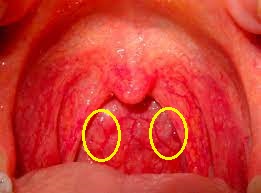

口の中をケガした場合、喉の方まで及んでいることがあります。

特に何かを咥えていて転んだときに、必ず喉の奥を調べる事が大事です。

喉の奥には、内頸動脈という脳へ酸素や栄養を運ぶ血管があります。

万が一これを損傷すると、命に関わる事態になってしまう事も否定できません。

命に別状は無くとも、脳梗塞などで、大きな障害を残す危険性もあります。